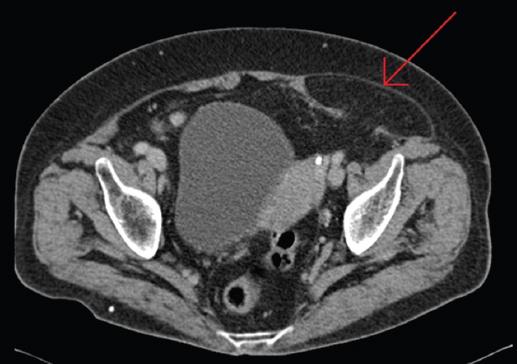

- Tomografía computarizada (TC): Método de elección para confirmar la localización y el contenido de la hernia.

Su disposición anatómica entre las diferentes capas músculoaponeuróticas de la pared abdominal dificulta su palpación, por lo que también es conocida como hernia oculta.

La mayor dificultad para su diagnóstico se encuentra cuando el saco herniario se halla reducido y no es posible palpar el orificio herniario o ni siquiera es apreciable una zona de sensibilidad dolorosa sugestiva en el momento de la exploración. Por lo que ante la sospecha clínica es recomendable el uso de pruebas complementarias para su diagnóstico.